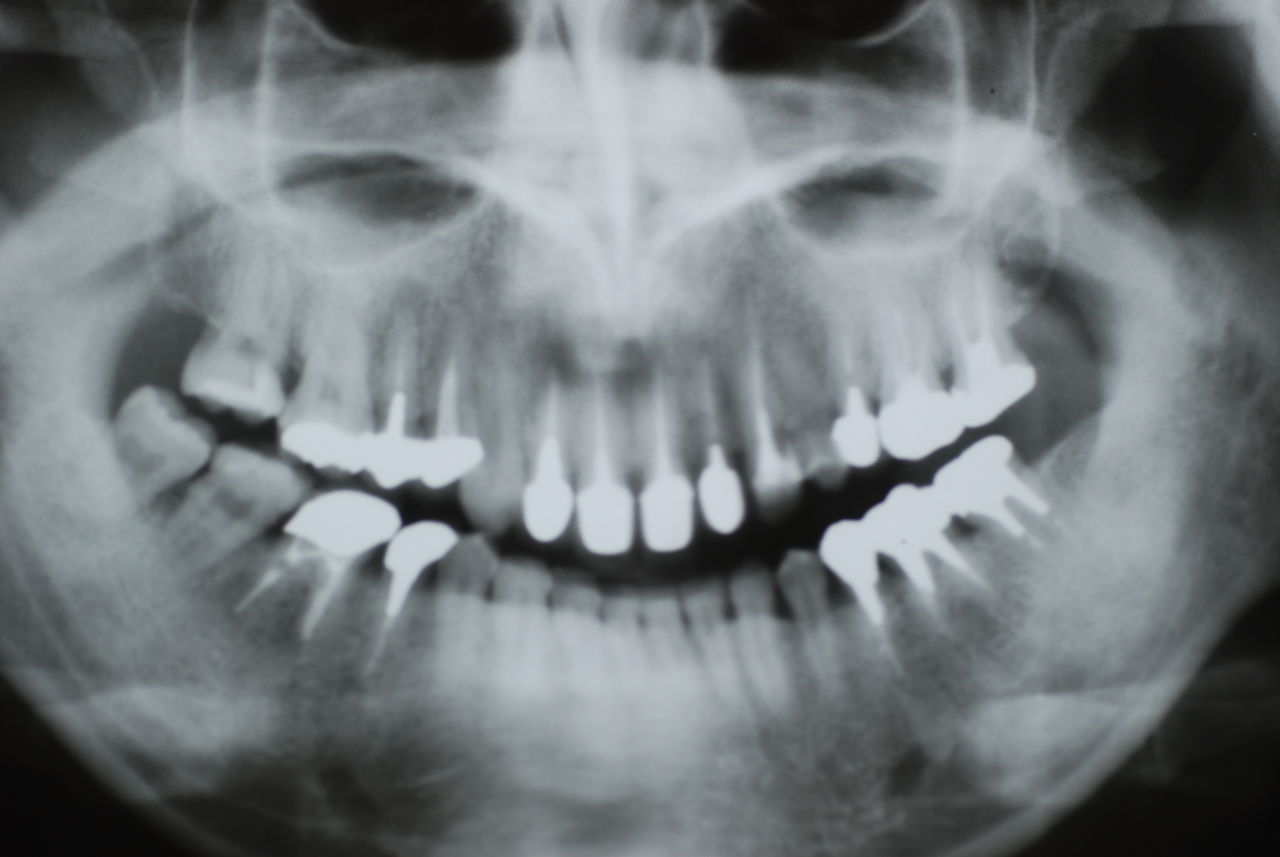

隣の14歳大臼歯がひどい虫歯になり治療不可能になりつつある状態のレントゲン

レントゲンでは小さいですが、こう言う虫歯が一番怖いのです。